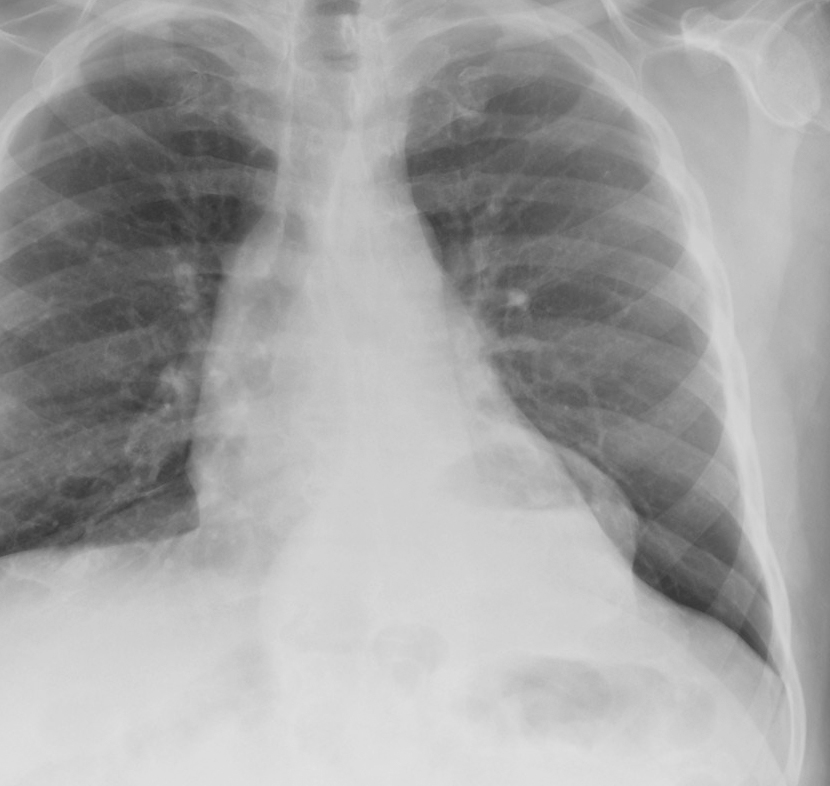

Mediastinum

Hiatus Hernia

Hiatus Hernia Case 7 PA

Case 7 PA